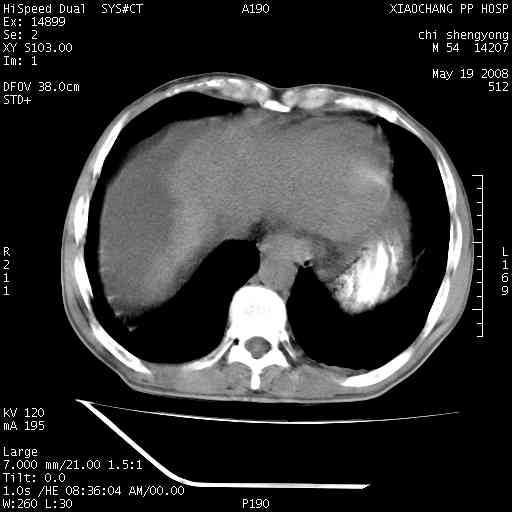

以下是引用zjzjr在2008-5-21 10:52:00的发言:[br]肝左叶巨块型肝癌伴门静脉左支瘤栓形成.肝硬化、腹水,胃底静脉曲张,脾术后改变。

以下是引用随光逐影在2008-5-21 16:20:00的发言:[br]1)肝左叶肝癌伴门静脉左支瘤栓形成,腹膜后淋巴结转移。2)肝硬化、腹水、胃底静脉曲张。3)胆囊炎。4)脾脏缺如,为切除术后所致。